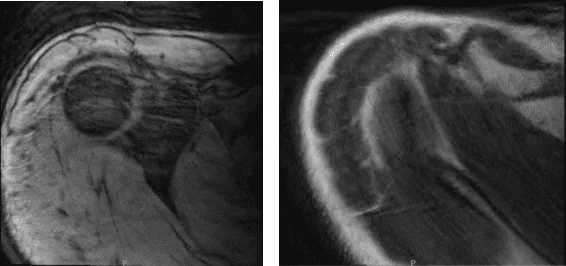

Se presentaron radiografías del hombro derecho e izquierdo. En el hombro derecho no hubo fracturas agudas, aunque hay un ensanchamiento asimétrico de la articulación acromioclavicular del hombro derecho y, para una evaluación adicional, se recomienda correlacionarse con la resonancia magnética. Por otro lado, la radiografía del hombro izquierdo mostró radiografías normales.

Radiografía del hombro derecho

Radiografía del hombro izquierdo

Dos semanas después de la operación, se realizó una resonancia magnética. La resonancia magnética del hombro derecho mostró esguince articular AC y tendinitis calcifica sospechosa del tendón supraespinoso.

Se recomienda repetir la correlación con radiografías o TAC para una evaluación definitiva. Se revisó la resonancia magnética del hombro izquierdo, se encontró desgarro parcial focal de bajo grado del tendón supraespinoso anterior y bursitis subdeltoidea subacromial leve.

MRI-3T Hombro derecho sin contraste

MRI-3T Hombro Izquierdo sin contraste